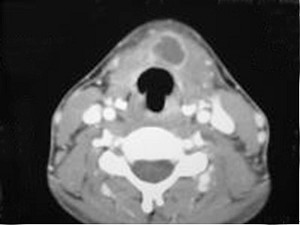

八歲患者,男性,因頸前正中包塊6年入院,查體:頸前正中舌骨下方可觸及一圓形包塊,囊性,無壓痛,隨吞咽上下活動。

8.患者腫塊圖像及影像學檢查結果見下圖,本患者應考慮為  (    )

9.如果考慮為你所選的上述疾病,手術前應該完善下面那個檢查  (    )

正確答案:8.A;9.A